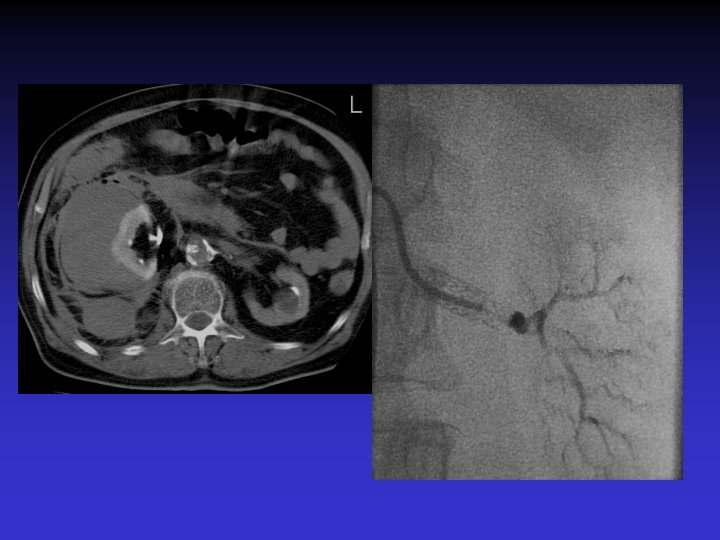

• 60 -year old male. • Hypertension (180/100) • 3 anti-HTN medications • Cr: 2, 1 mg/dl

• Normotensive • Cr=1. 1 mg/dl with one medication. Herculink 6 X 18 -mm

Case # 2 • 50 -year-old male with solitary kidney. • Smoker. • Refractory HTN. • Cr: 3. 8 mg/dl

• B/P: 160/80 mm. Hg • Cr: 1. 8 mg/dl